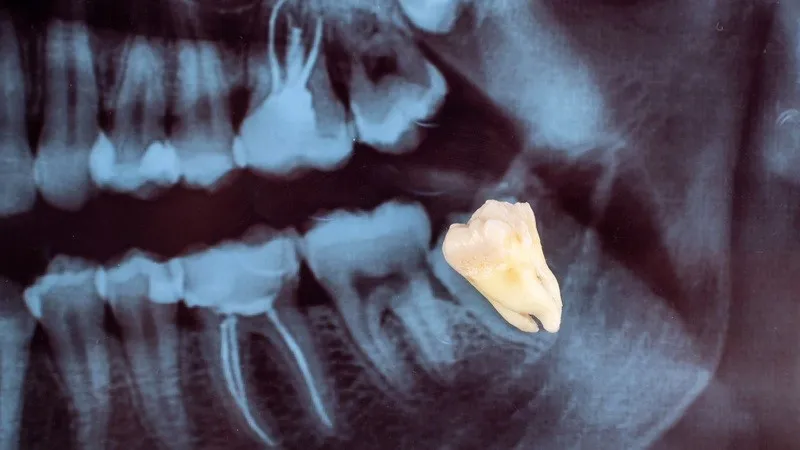

Đây là tình trạng khi một chiếc răng không thể mọc lên hoàn toàn để lộ ra ngoài bề mặt nướu, mà bị kẹt lại trong xương hàm hoặc mô mềm xung quanh. Điều này thường xảy ra khi không đủ không gian trong cung hàm để răng phát triển hoặc do răng bị lệch hướng trong quá trình mọc.

Tình trạng này phổ biến nhất ở răng khôn (răng số 8), nhưng cũng có thể xảy ra ở các răng khác như răng nanh hay răng hàm nhỏ. Răng mọc ngầm không chỉ gây đau nhức mà còn tiềm ẩn nhiều nguy cơ như viêm nhiễm, hư hại các răng lân cận hoặc làm thay đổi cấu trúc hàm.

Răng mọc ngầm là gì

Răng bị mọc ngầm là tình trạng răng không thể mọc lên trên bề mặt nướu